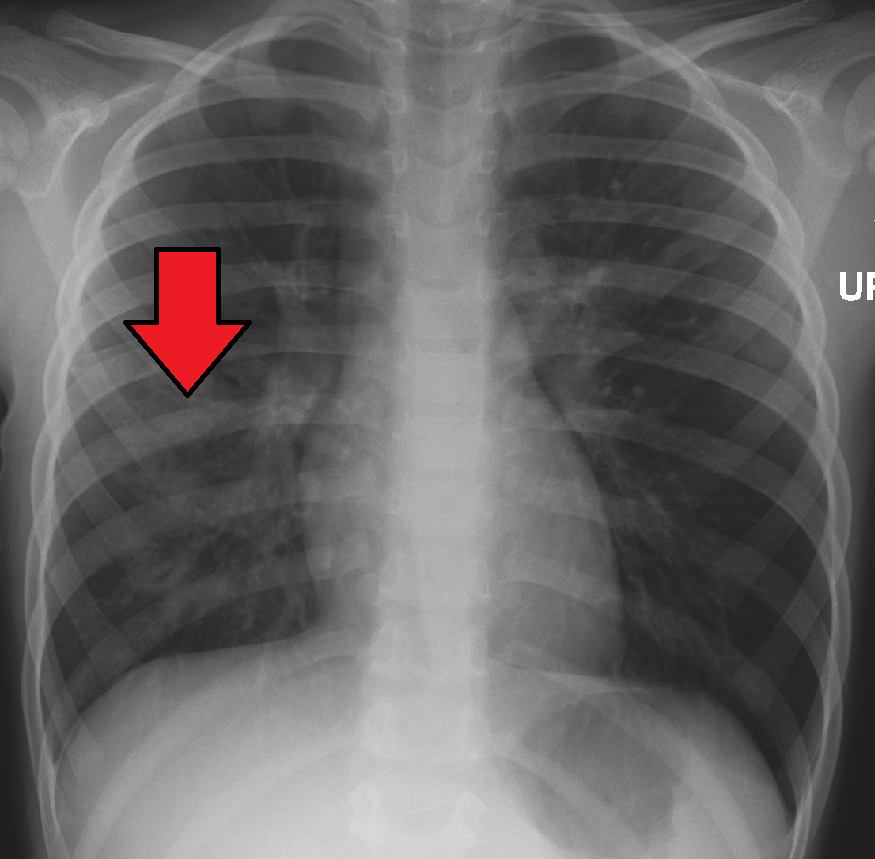

흉부 방사선 사진은 폐렴 진단에 흔히 사용된다.[141] 경증 환자는 잠재적 합병증이 있거나, 치료에 호전되지 않거나, 원인이 불확실한 경우에만 영상 검사가 필요하다.[141][65] 입원이 필요할 정도로 중증인 경우 흉부 방사선 사진이 권장된다.[65] 방사선 소견이 항상 질병의 중증도와 일치하지는 않으며, 세균성과 바이러스성 감염을 확실하게 구분하지 못한다.[141]

폐렴의 X선 사진 소견은 섬엽 폐렴, 세기관지 폐렴, 소엽 폐렴, 간질성 폐렴으로 분류할 수 있다.[66] 세균성, 급성 폐렴은 고전적으로 폐 분절엽 하나의 폐 실질 침윤을 보이는데, 이를 섬엽 폐렴이라고 한다.[72] 그러나 소견은 다양할 수 있으며, 다른 유형의 폐렴에서는 다른 양상이 흔하다.[72] 흡인성 폐렴은 주로 폐 아래쪽과 오른쪽에 양측성 음영으로 나타날 수 있다.[72] 바이러스성 폐렴의 X선 사진은 정상, 과팽창, 양측성 반점, 또는 섬엽 폐렴과 유사한 폐 실질 침윤으로 나타날 수 있다.[72] 특히 탈수가 있는 경우 질병 초기에는 방사선학적 소견이 없거나, 비만 또는 폐 질환 병력이 있는 사람은 해석하기 어려울 수 있다.[140] 흉막 삼출과 같은 합병증도 흉부 방사선 사진에서 발견될 수 있다. 측면 흉부 방사선 사진은 폐 실질 침윤과 흉막 삼출 진단 정확도를 높일 수 있다.[78]